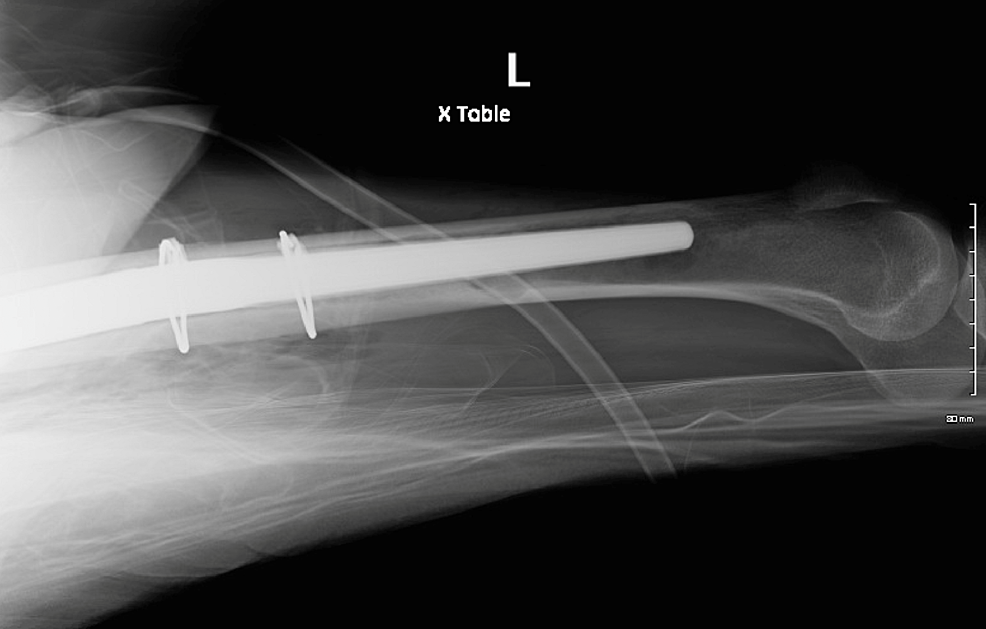

IM Rod Femur What Is A Prophylactic Fixation Several methods exist to predict the risk of pathologic fracture. Prophylactic fixation refers to operating on an impending pathologic fracture before it occurs to. prophylactic surgical stabilization is often recommended to prevent fracture rather than waiting for the. the aim is to evaluate and to highlight on value of prophylactic fixation of impending fractures in abnormal bone. . What Is A Prophylactic Fixation.